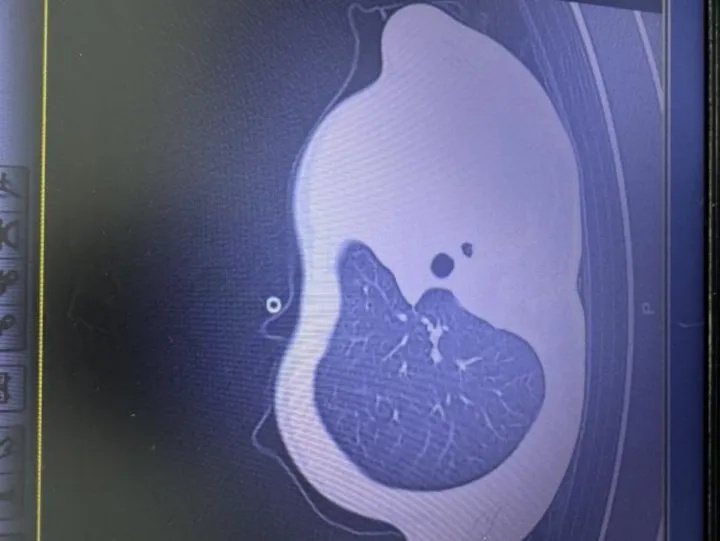

早上开始发烧,晚上就“白肺”了!

男孩连续两年因流感进ICU

医生:这4个信号是重症前兆

12月14日,浙江大学医学院附属儿童医院PICU收治一名因流感引发重症肺炎的11岁男孩。该患儿从发烧到出现“白肺”仅用一天时间,经诊断为流感合并细菌感染引发的坏死性喉气管支气管炎。

据主治医师介绍,患儿气道内充满痰栓导致严重缺氧,在ICU期间接受5次气管镜治疗并依靠呼吸机维持生命。这已是该患儿连续第二年因流感重症入院。

医生指出流感转向重症的四个关键警示信号:

◾持续高热不退:体温超过38.5℃,服用退烧药效果不佳

◾呼吸系统异常:咳嗽喘息加重,呼吸急促(学龄儿童>30次/分钟),口唇发紫

◾全身严重症状:剧烈胸痛、精神萎靡、无法平躺

◾危急生命体征:胸闷、呼吸困难、说话费力、意识障碍或抽搐

医生提醒,目前上海已进入流感高发期,建议重点人群及时接种疫苗。